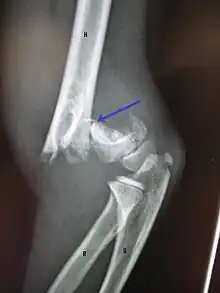

A displaced supracondylar fracture in a child